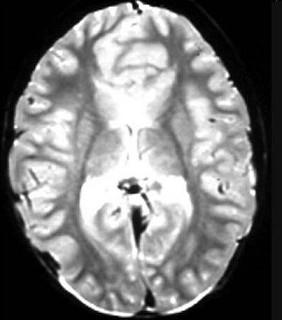

问题 根据MRI表现,考虑是何种先天性神经系统异常的疾病是 ( )

选项 A、灰质异位症 B、胼胝体发育不全 C、Dandy-Walker综合征 D、前脑无裂畸形 E、脊柱裂

答案 D